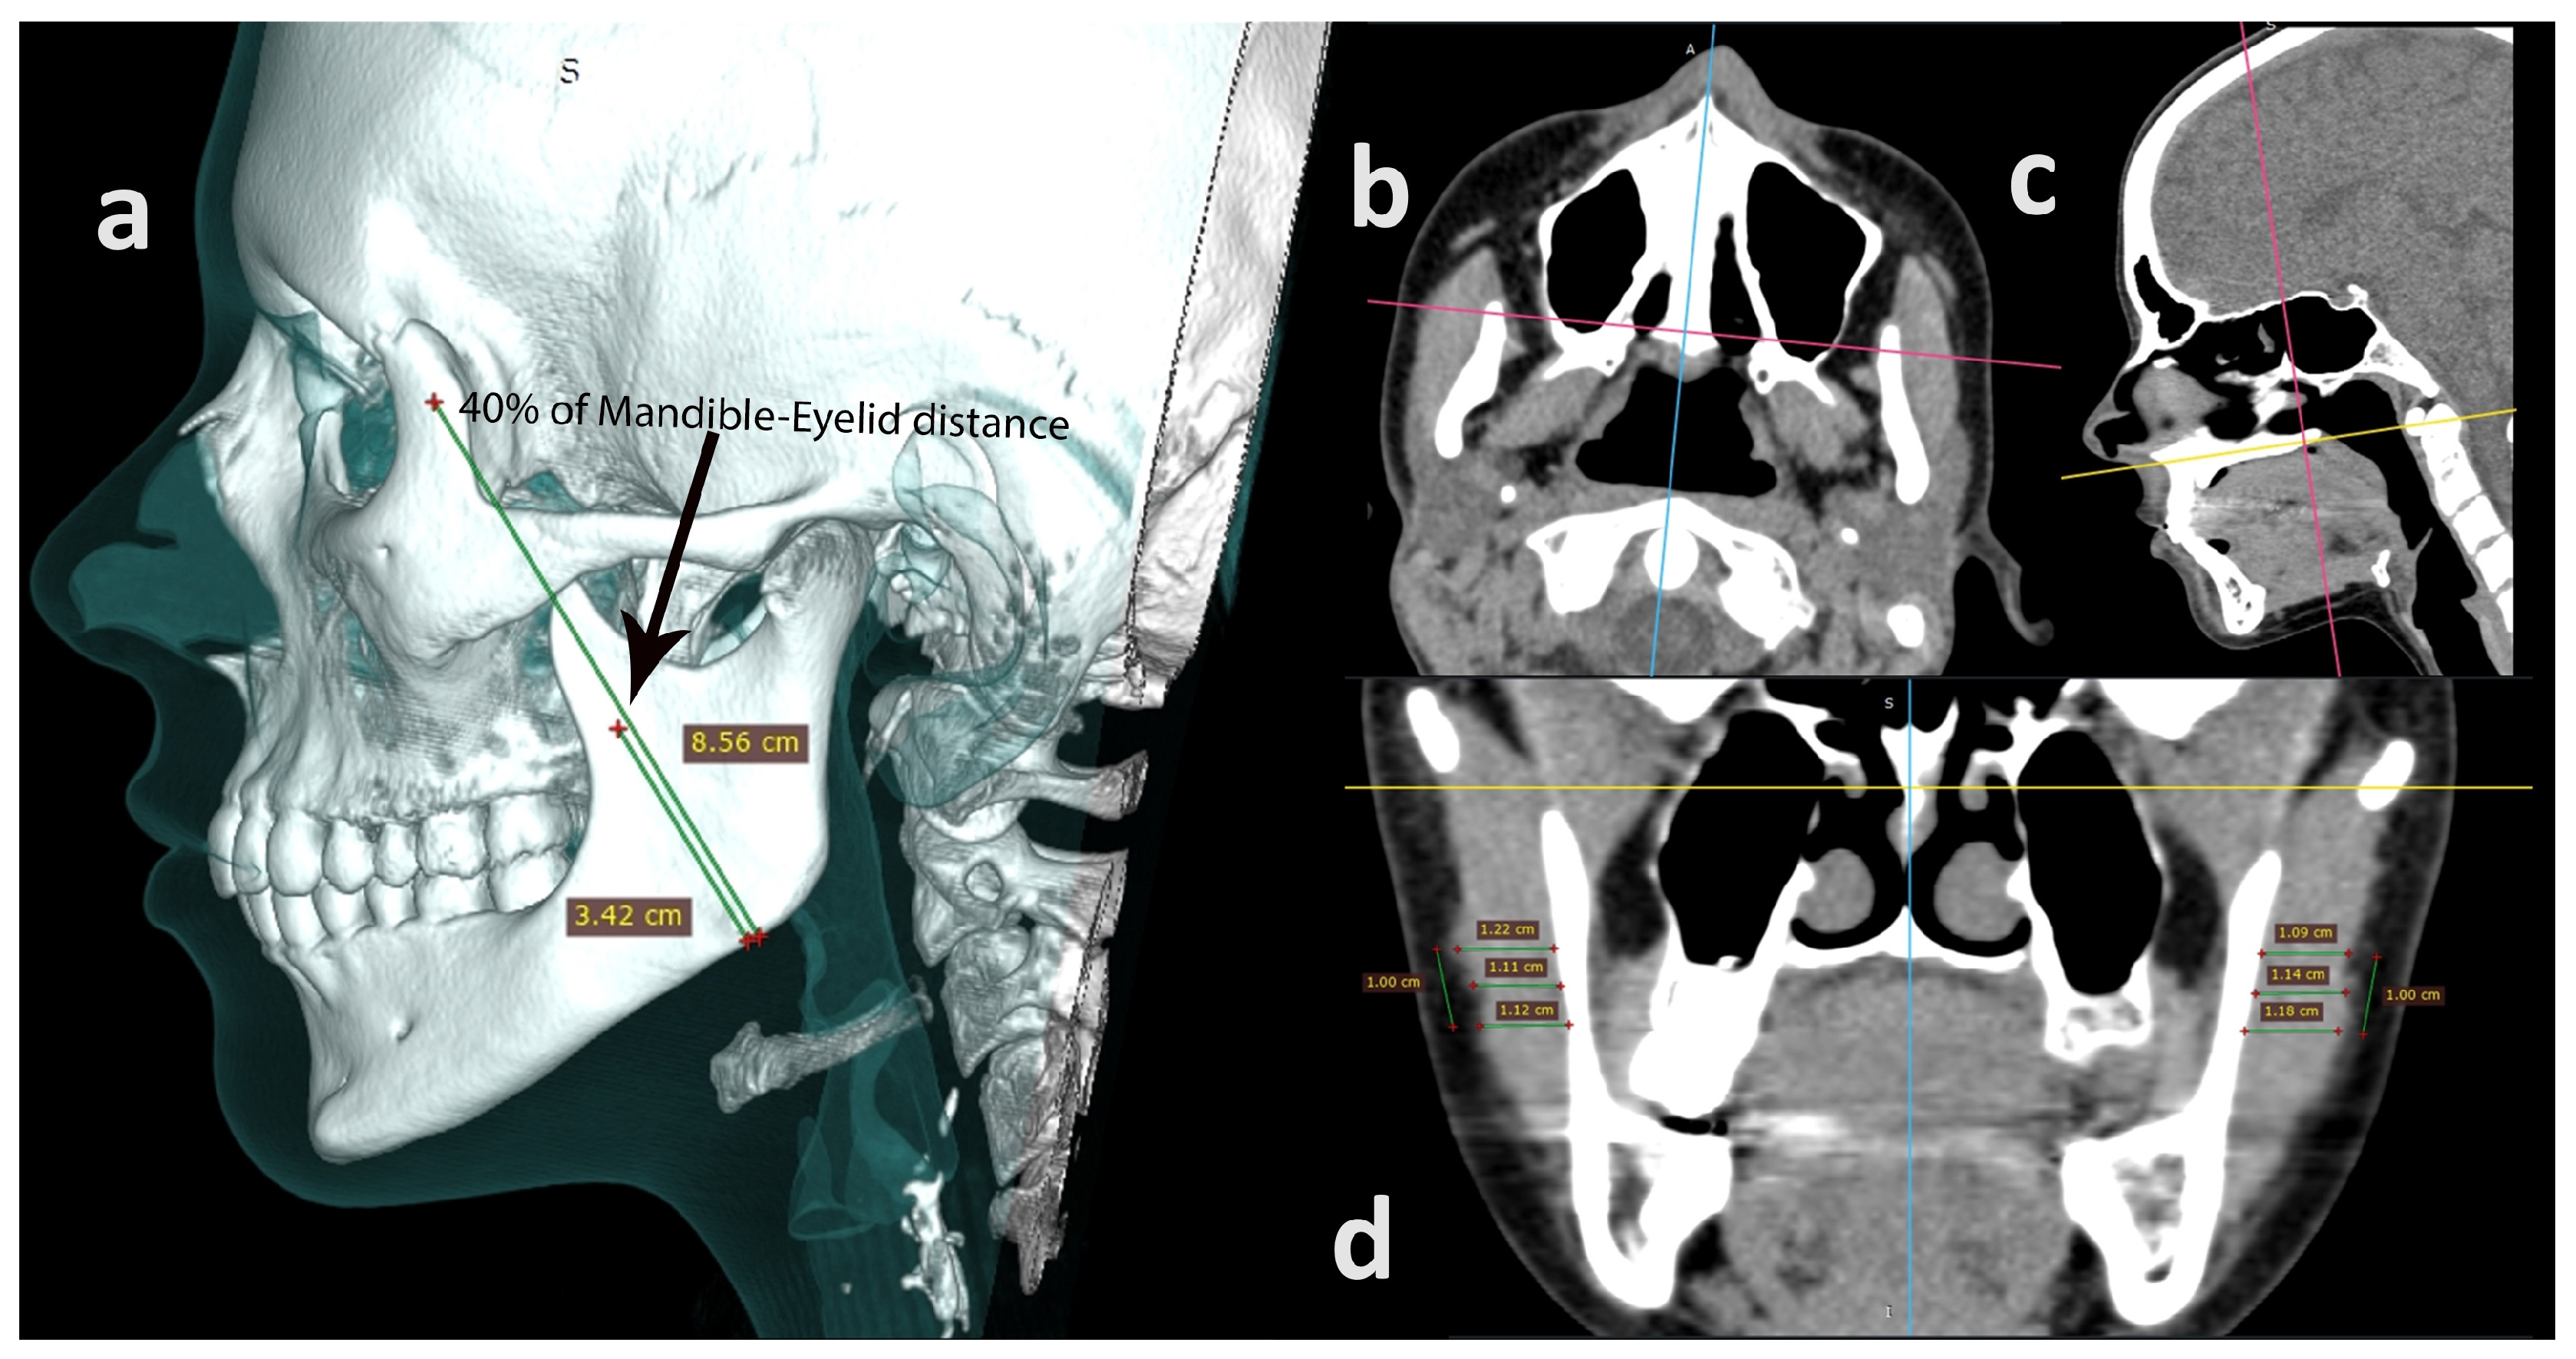

2.4. Computed Tomography

2.5.2. Computed Tomography

3.3. Mandible–Eyelid Distance